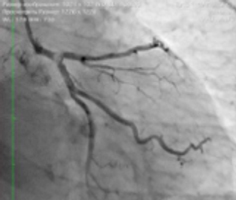

В рамках обследования ему была выполнена коронарография, на которой рентгенхирурги увидели массивную кальцинированную бляшку в терминальном отделе ствола левой коронарной артерии, перекрывавшую просвет артерии на 95%.

![]() Исходная коронарограмма |

Такое поражение было чревато обширным инфарктом с высокой степенью летальности, поскольку левая коронарная артерия снабжает кровью более 70% миокарда. Еще 10 лет назад такое поражение являлось строгим показанием к аорто-коронарному шунтированию. Однако надо понимать, что средняя продолжительность функционирования венозных шунтов 15 лет, а пациент достаточно молод. |